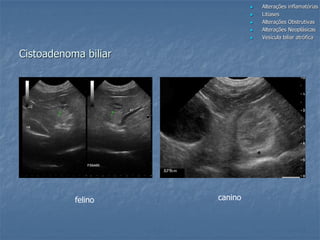

Cistoadenoma biliar

gato

felino

canino